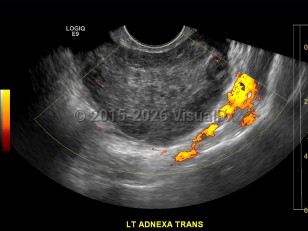

Ovarian torsion

Ovarian torsion is an acute condition that can be a true gynecologic emergency. It occurs when an ovary twists on the adjacent infundibulopelvic ligament, causing disruption of blood supply to the ovary and in effect creating a tourniquet. Torsion accounts for 2.7% of all gynecologic emergencies. It is more common in women 20-30 years of age, but it can occur at any age from early childhood (rare) to after menopause. Ovarian torsion more commonly occurs on the right side.

Risk factors include ovarian cyst with size greater than 4-6 cm or with solid components, history of prior torsion, pregnancy, and history of pelvic surgery. Patients may not have had a history of ovarian cysts prior.